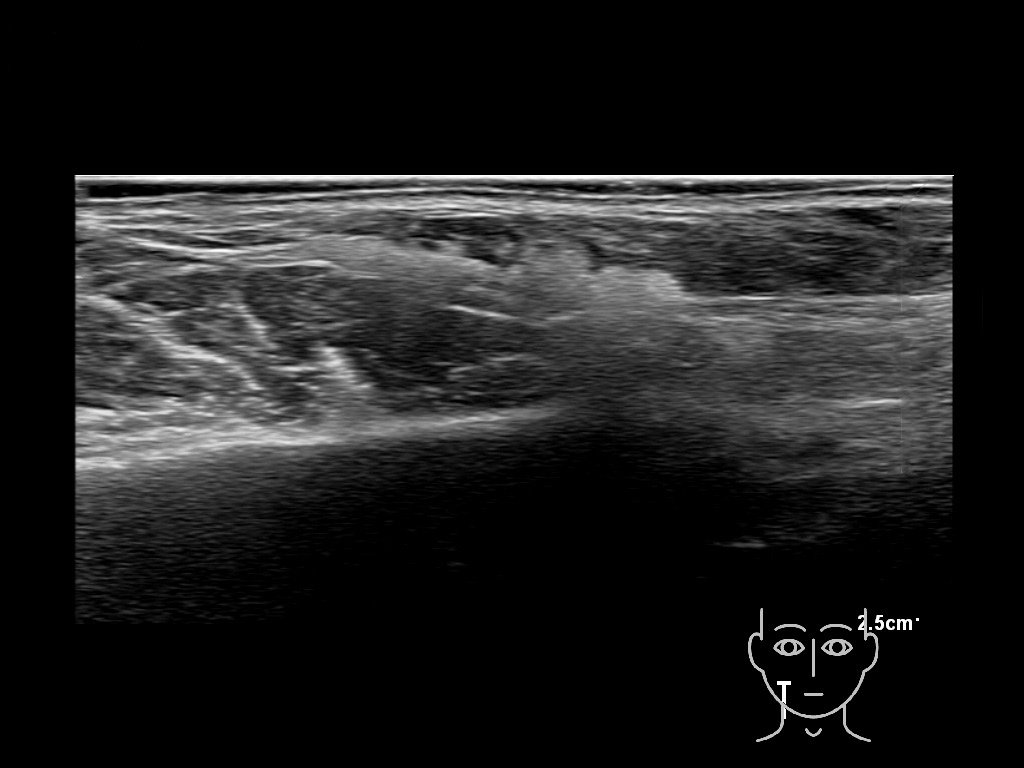

haca 0

HAca 10a